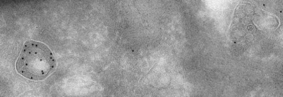

| Applications: | WB/IF/IHC-P/IHC-F/IEM |

| Dilution Range: | WB 1:250-1:1000IF 1:50-1:200IHC-P 1:200-1:1000IHC-F 1:200-1:1000IEM 1:50-1:200Romagnoli M Bresson L Di-Cicco A et al. Development 2020 Jan. PMID: 31988184Pelkonen L Sato K Reinisalo M et al. Mol Pharm 2017 Mar. PMID: 281 |